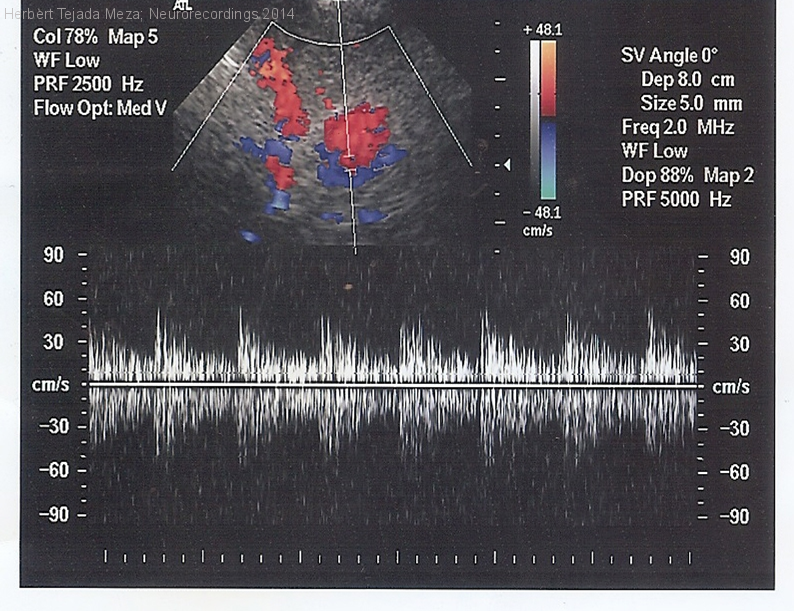

Aneurisma de arteria basilar asociado a accidentes isquémicos transitorios de repetición

Diagnóstico final: Aneurisma sacular de arteria basilar parcialmente trombosado